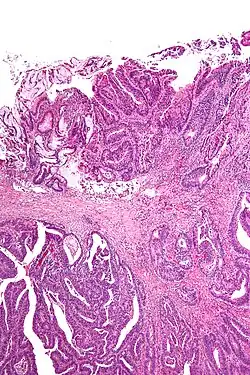

Resection margin

A resection margin or surgical margin is the edge or "margin" of apparently non-tumorous tissue around a tumor that has been surgically removed, called "resected", in surgical oncology. The resection is an attempt to remove a cancer tumor so that no portion of the malignant growth extends past the edges or margin of the removed tumor and surrounding tissue. These are retained after the surgery and examined microscopically by a pathologist to see if the margin is indeed free from tumor cells (called "negative"). If cancerous cells are found at the edges (called "positive") the operation is much less likely to achieve the desired results.[1]: sections 1-2

Surgical margin in a surgery report defines the visible margin or free edge of "normal" tissue seen by the surgeon with the naked eye. Surgical margin as read in a pathology report defines the histological measurement of normal or unaffected tissue surrounding the visible tumor under a microscope on a glass mounted histology section.[4][5] A "narrow" surgical margin implies that the tumor exists very close to the surgical margin, and a "wide" surgical margin implies the tumor exists far from the cut edge or the surgical margin. Narrow surgical margin using the bread loafing technique suggests that residual cancer might be left due to false negative error. A surgeon often will perform a second surgery if a narrow surgical margin is noted on a pathology report.